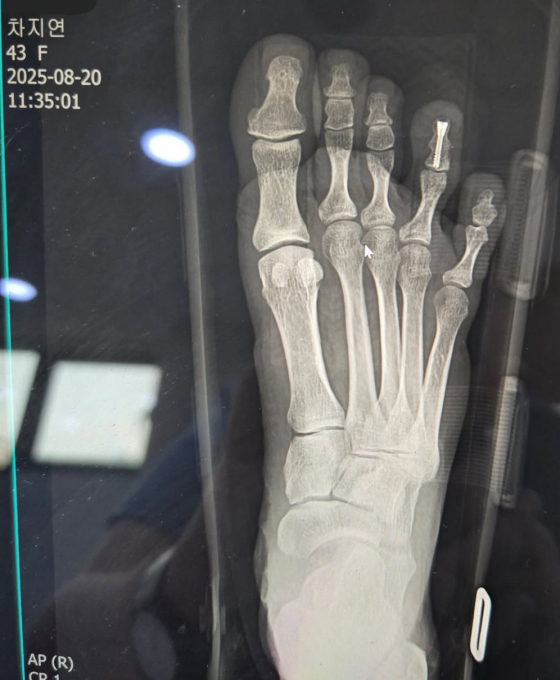

차지연은 이와 함께 부상 당한 발 엑스레이 사진을 공개하기도 했다.

28일 차지연은 개인 SNS를 통해 "제 소식을 들으시고 많이 놀라셨을 여러분들께 먼저 죄송하다는 말씀드린다"며 "공연 연습 도중 오른쪽 네 번째 발가락을 심하게 부딪힌 뒤 통증이 심해서 급히 응급실에 가본 결과 골절 진단을 받고 순간 심장이 덜컹했습니다. 오로지 공연에 대한 생각 외에는 아무것도 생각나지 않았다"고 밝혔다.

그는 "다음 날 일찍 바로 나사를 박는 수술을 했고 오늘이 일주일이 되는 날이고 회복에 전념 중"이라며 "수술 이후 무리 없이 활동을 할 수 있는 시기는 6주 진단으로 받았지만 기다려주신 관객분들과 애써주신 창작진분들 그리고 제작진분들께도 큰 피해가 되고 있는 것을 누구보다 잘 알고 있기에 하루라도 빨리 복귀를 하고 싶은 마음만 간절했다"고 토로했다.